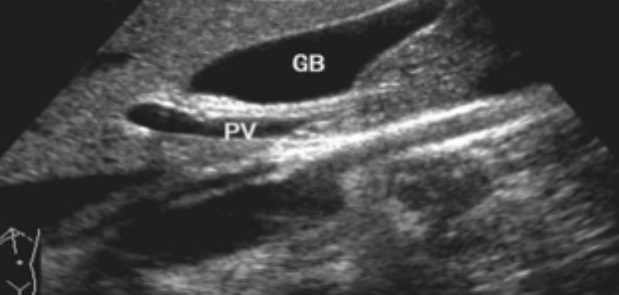

一、正常胆囊超声图像有的时候经常发现检查不到胆囊,其实有几种可能性,检查人员的技术不过关没发现胆囊,就要找上级医生会诊,如果还是没找到的话就不是技术问题。结石或肿瘤充满胆囊,使其液腔消失,慢性胆囊炎使得胆囊萎缩或胆囊壁肥厚而囊腔消失患者已进食,胆囊处于胆汁排空的状态,胆囊先天性过小或缺失;胆囊位置极端异常(可能很低或位于左侧)胆囊切除术后(注意询问病史)。